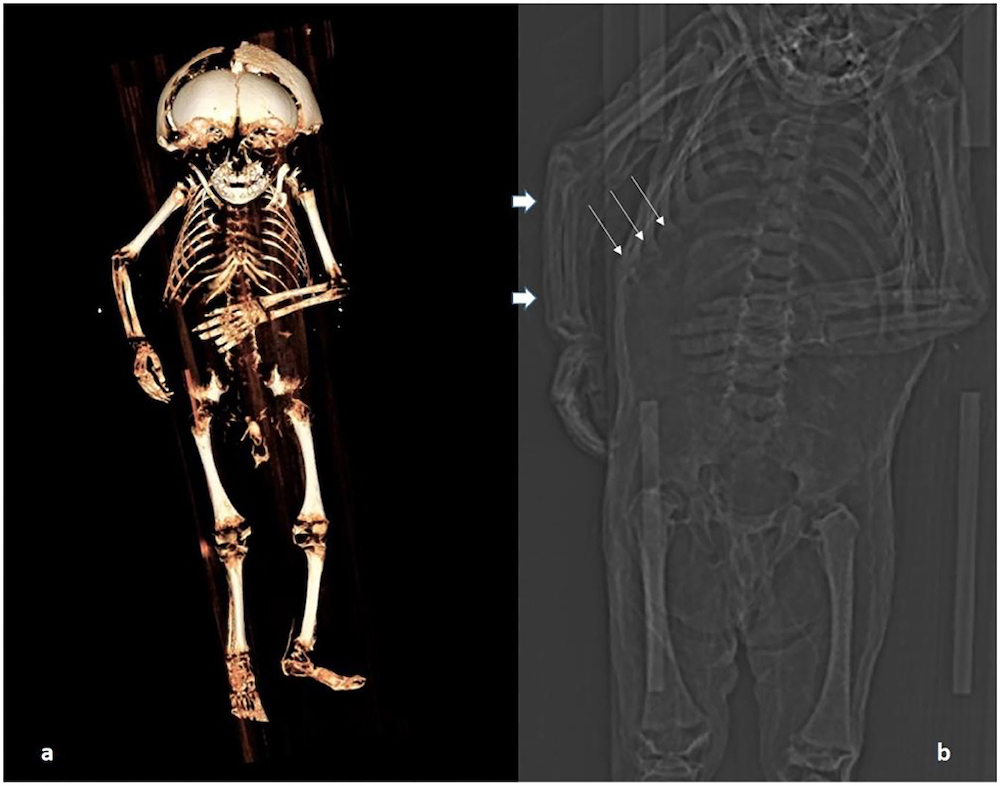

Este equipo analizó el cuerpo de un niño —de casi dos años de edad— momificado en el siglo XVI, en Austria. Se creía que la causa de la muerte había sido por falta de vitamina C.

¿Cómo llegaron a esa primera conclusión? Antes de este análisis, ya habían hecho una autopsia al cuerpo del niño por malformaciones en las costillas.

Justo este fue el elemento que hizo que pensaran que el niño había muerto por desnutrición o raquitismo —debilitamiento de los huesos— a falta de vitamina C.

Pero llegó otro análisis, esta vez del tejido adiposo que arrojó pruebas de que el niño nunca enfrentó problemas de alimentación. Es más, que estaba bien alimentado en comparación a otros bebés de su época —el niño murió entre 1550 y 1635.